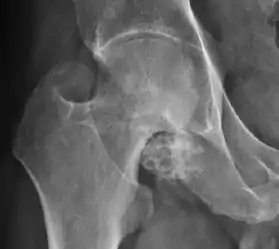

Plain radiography allows us to categorize the hip as normal or dysplastic or with impingement signs (pincer, cam, or a combination of both). Besides these, pathologic processes like osteoarthritis, inflammatory diseases, infection, or tumors can also be identified (Figure 1).[1]

Figure 1.

Synovial chondromatosis can be confidently diagnosed by X-ray when calcified cartilaginous chondromas are seen. However, other synovial proliferative processes, such as pigmented villonodular synovitis, require MRI for accurate diagnosis, although noncalcified synovitis can be suspected in radiographs by indirect signs, such as soft tissue swelling and/or erosions in the femoral head, femoral neck, or acetabulum (Figure 7).[1]

Figure 7:

- X-ray of synovial chondromatosis.[1]